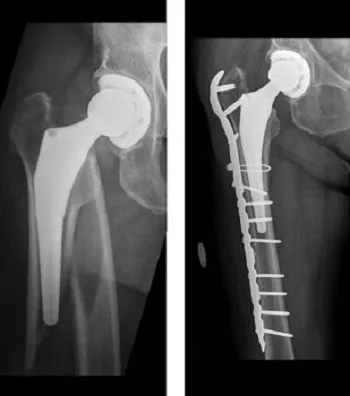

1. Fixatie van de breuk (osteosynthese): Als de bestaande heupprothese nog stevig vastzit in het bot, zal de chirurg proberen de botbreuk te herstellen zonder de prothese te vervangen. Dit gebeurt door middel van osteosynthese: het plaatsen van platen, schroeven en kabels rondom de prothese om de botfragmenten te fixeren. Bijvoorbeeld: bij een breuk net onder een goed gefixeerde heupprothese plaatst men vaak een sterke metalen plaat langs de buitenzijde van het dijbeen, die met meerdere schroeven boven en onder de breuk de botdelen overbrugt. Vaak worden ook cerclagedraden of kabels gebruikt om broze botstukken extra vast te klemmen. De prothese zelf blijft op zijn plaats. Deze techniek is minder ingrijpend dan een prothesewissel en behoudt het eigen implantaat. Belangrijk is dat de kwaliteit van het bot en de breukconfiguratie een stabiele fixatie toelaat.

2. Revisie van de heupprothese: Als de heupprothese losgeschoten of instabiel is door de fractuur, of als de breuk op zo’n manier zit dat fixatie niet volstaat, kiest men voor een revisieoperatie. Dit betekent dat (een deel van) de bestaande prothese wordt verwijderd en vervangen door een nieuw implantaat dat de breukzone overbrugt. Meestal zal de chirurg een nieuwe langere steel in het dijbeen plaatsen die voorbij de breuk reikt, zodat het bot weer van binnenuit gesteund wordt. Zelden is het nodig dat ook de heupkom-component vervangen wordt. Bij de meeste revisies wordt een langere heupprothese gebruikt en een plaat om de breuk te fixeren. Na een prothesewissel is het bot direct intern gesteund door de nieuwe prothese, maar de breuk moet nog steeds genezen rondom de prothesesteel.